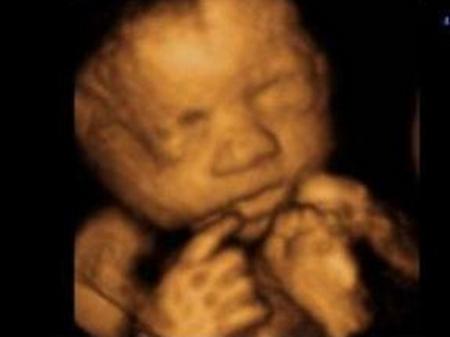

最后来个可爱的四维照!

有没有觉得宝宝可爱到爆!